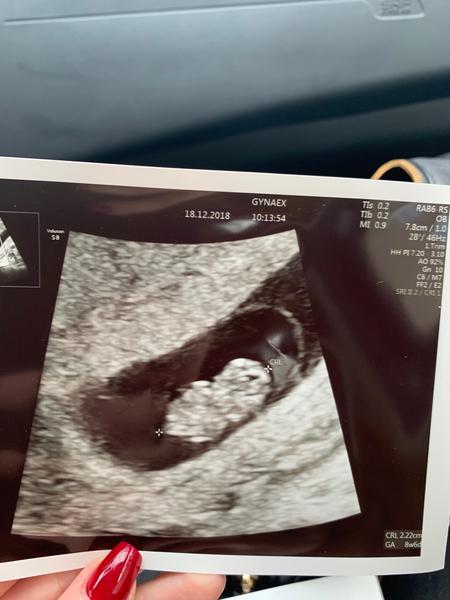

@shimmikk krása 😍👶

@shimmikk fazulka 😍😍😋🤗